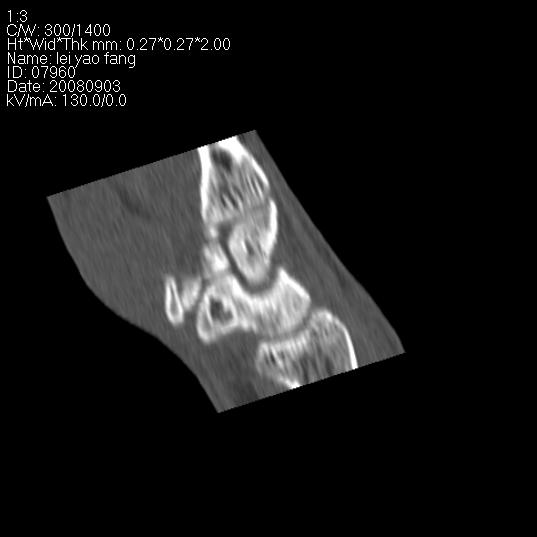

以下是引用杀毒软件在2008-9-4 17:41:00的发言:[br]考虑----舟骨囊肿